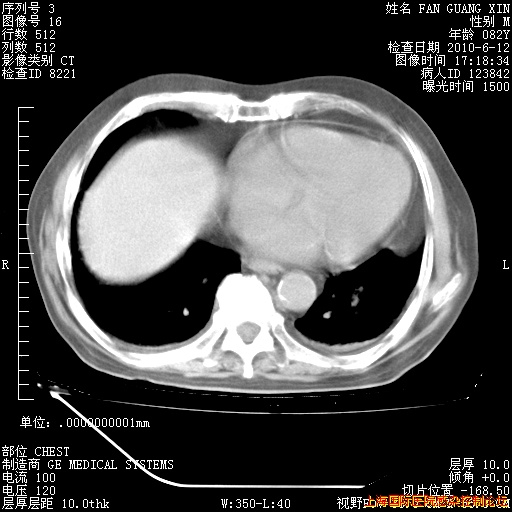

6月12日纵膈窗

整整相隔30天的肺部CT好像有所好转啊。甲强龙减量第3天,需要观察体温。